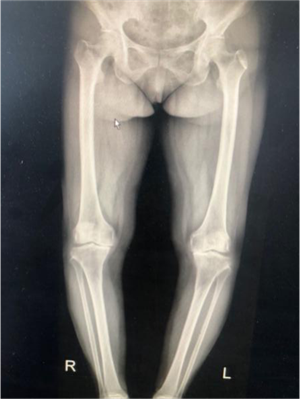

67歲的徐女士是陜北定邊縣人,10年來,她因為雙膝關節(jié)疼痛,行走困難,不能上下樓梯,更無法像常人一樣下蹲,這給徐阿姨和她的家庭帶來了巨大的困擾。經(jīng)多方打聽,徐阿姨慕名找到張富軍主任,張主任詳細檢查后發(fā)現(xiàn)徐阿姨為雙側(cè)嚴重的骨關節(jié)炎并滑膜軟骨瘤病,需要進行全膝關節(jié)置換術??紤]到患者有多種基礎病合并癥,張主任帶領其團隊認真研究后制定了詳細、周密的手術方案,做好圍手術期的準備,決定采用最新技術的Vanguard CR E1假體雙膝膝關節(jié)置換術。

?。ㄊ中g前、手術后對比)

5月29日,徐阿姨如期進行了雙側(cè)全膝關節(jié)同期置換術。術中發(fā)現(xiàn)徐阿姨膝關節(jié)退變嚴重,有大量的滑膜軟骨瘤,清除病變后又發(fā)現(xiàn)她前交叉韌帶缺失后交叉韌帶纖細,即決定采用限制性較高的E1 AS墊片,該假體極大的提高了手術安全性,降低了手術風險和創(chuàng)傷,手術歷時2小時,患者術后恢復良好。手術后第二天,徐阿姨就可以扶著助步器下地活動,目前已可以徒步行走、上下樓梯。